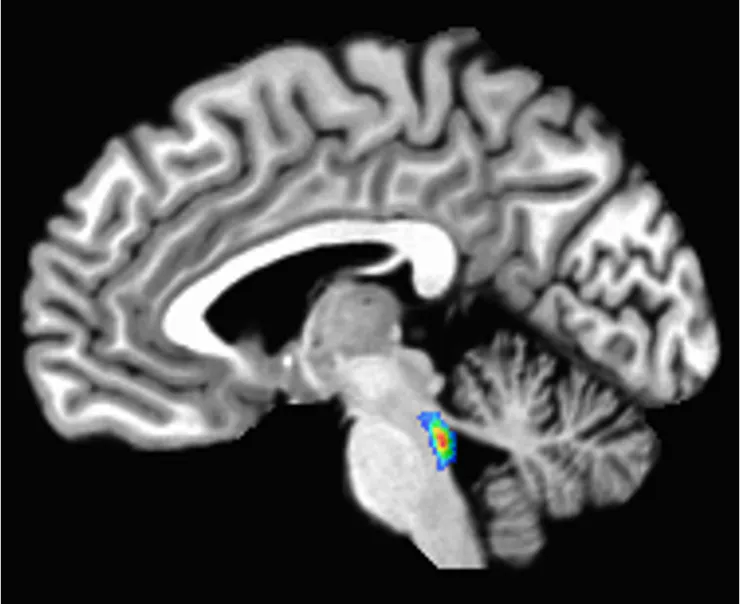

In the earliest of these changes, a tangled version of a protein called tau starts building up in a tiny region deep in the brain involved in sleep, attention and alertness, called the locus coeruleus. Tau later spreads to the rest of the brain.

Developing tau tangles doesn’t mean a person has Alzheimer’s disease – in fact, it happens to nearly everyone to varying degrees. But because these changes start in the locus coeruleus, some brain researchers – myself included – see this area as a canary in the coal mine for developing Alzheimer’s disease

The locus coeruleus sits in the brain stem, the lowest part of the brain. Its name, “blue spot,” comes from a pigment called neuromelanin that its cells produce.

Studies suggest that starting in middle age, nerve cells in the locus coeruleus may get damaged by tau buildup, and that damage may correlate with declines in memory. Tau buildup, cell death and loss of function in the locus coeruleus precedes and predicts Alzheimer’s diagnosis and symptoms.